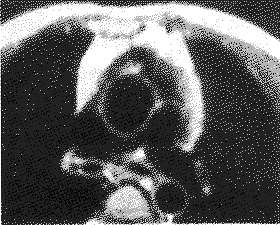

肺动脉狭窄 漏斗部、肺动脉主干狭窄及左右肺动脉分支发育情况在横轴位上均能良好显示(图4)。在矢状位或斜矢状位可较清楚观察到右室流出道狭窄及狭窄的程度和类型(图5)。在横轴上行cine-MRI,均能更加清晰显示狭窄的右室流出道、肺动脉主干、左右肺动脉起始及远端走形的情况(图6),14例能显示左/右肺动脉的一级分支。本组3例CAG左肺动脉显示不清楚,难以定论,而MRI及cine-MRI能较好显示左肺动脉发育情况,分别诊断为左肺动脉起始部局限性狭窄,左侧肺动脉普遍发育不良(图7)及左肺动脉缺如(图8),均经手术证实。MRI、UCG及CAG分别对主动脉和主肺动脉以其分支内径进行测量,其测量值见表2。3种影像学方法测量值经相关分析均有显著性,结果显示主肺动脉和主动脉相关程度较高,左、右肺动脉的相关程度较低但相关有显著性)见表3。

图4 MRI横轴位 清楚显示狭窄的右室流出道,主

肺动脉及左/右肺动脉的全貌